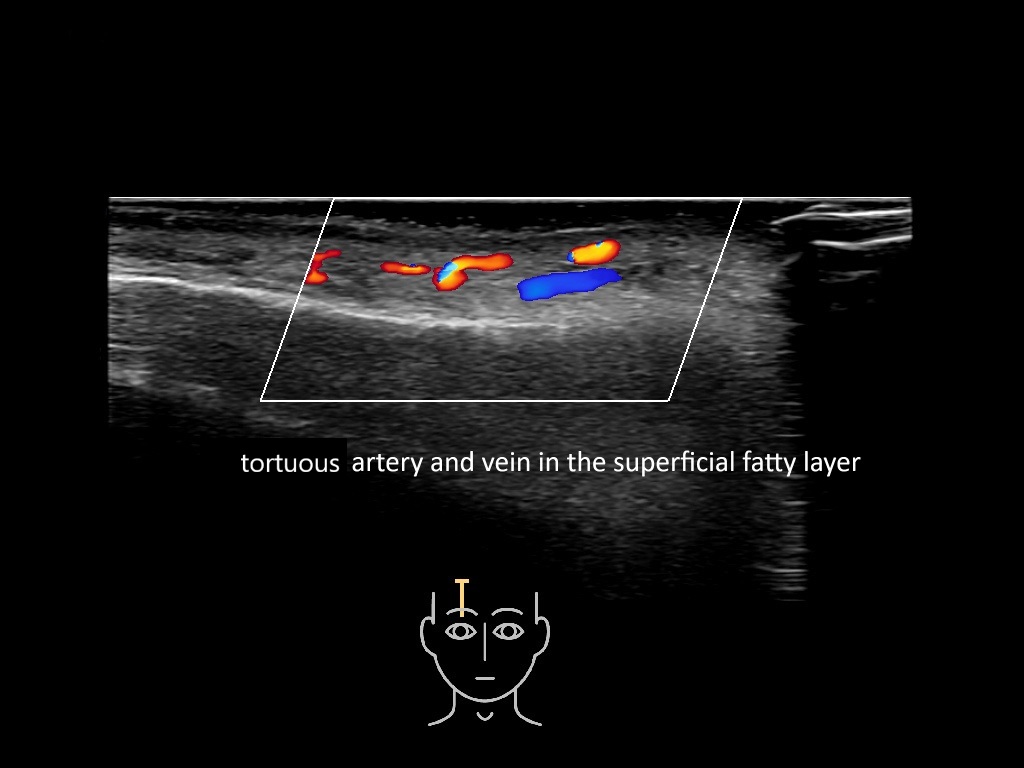

In this section you will learn more about the different layers of the face with the use of ultrasound. When you click on the secondary ultrasound image, you will see the different structures as an overlay. This will help to train yourself to recognize the different layers of the face.

Study the first image to recognize the different layers. If you are sure about the layers, swipe to the second image to view the answer (if applicable).